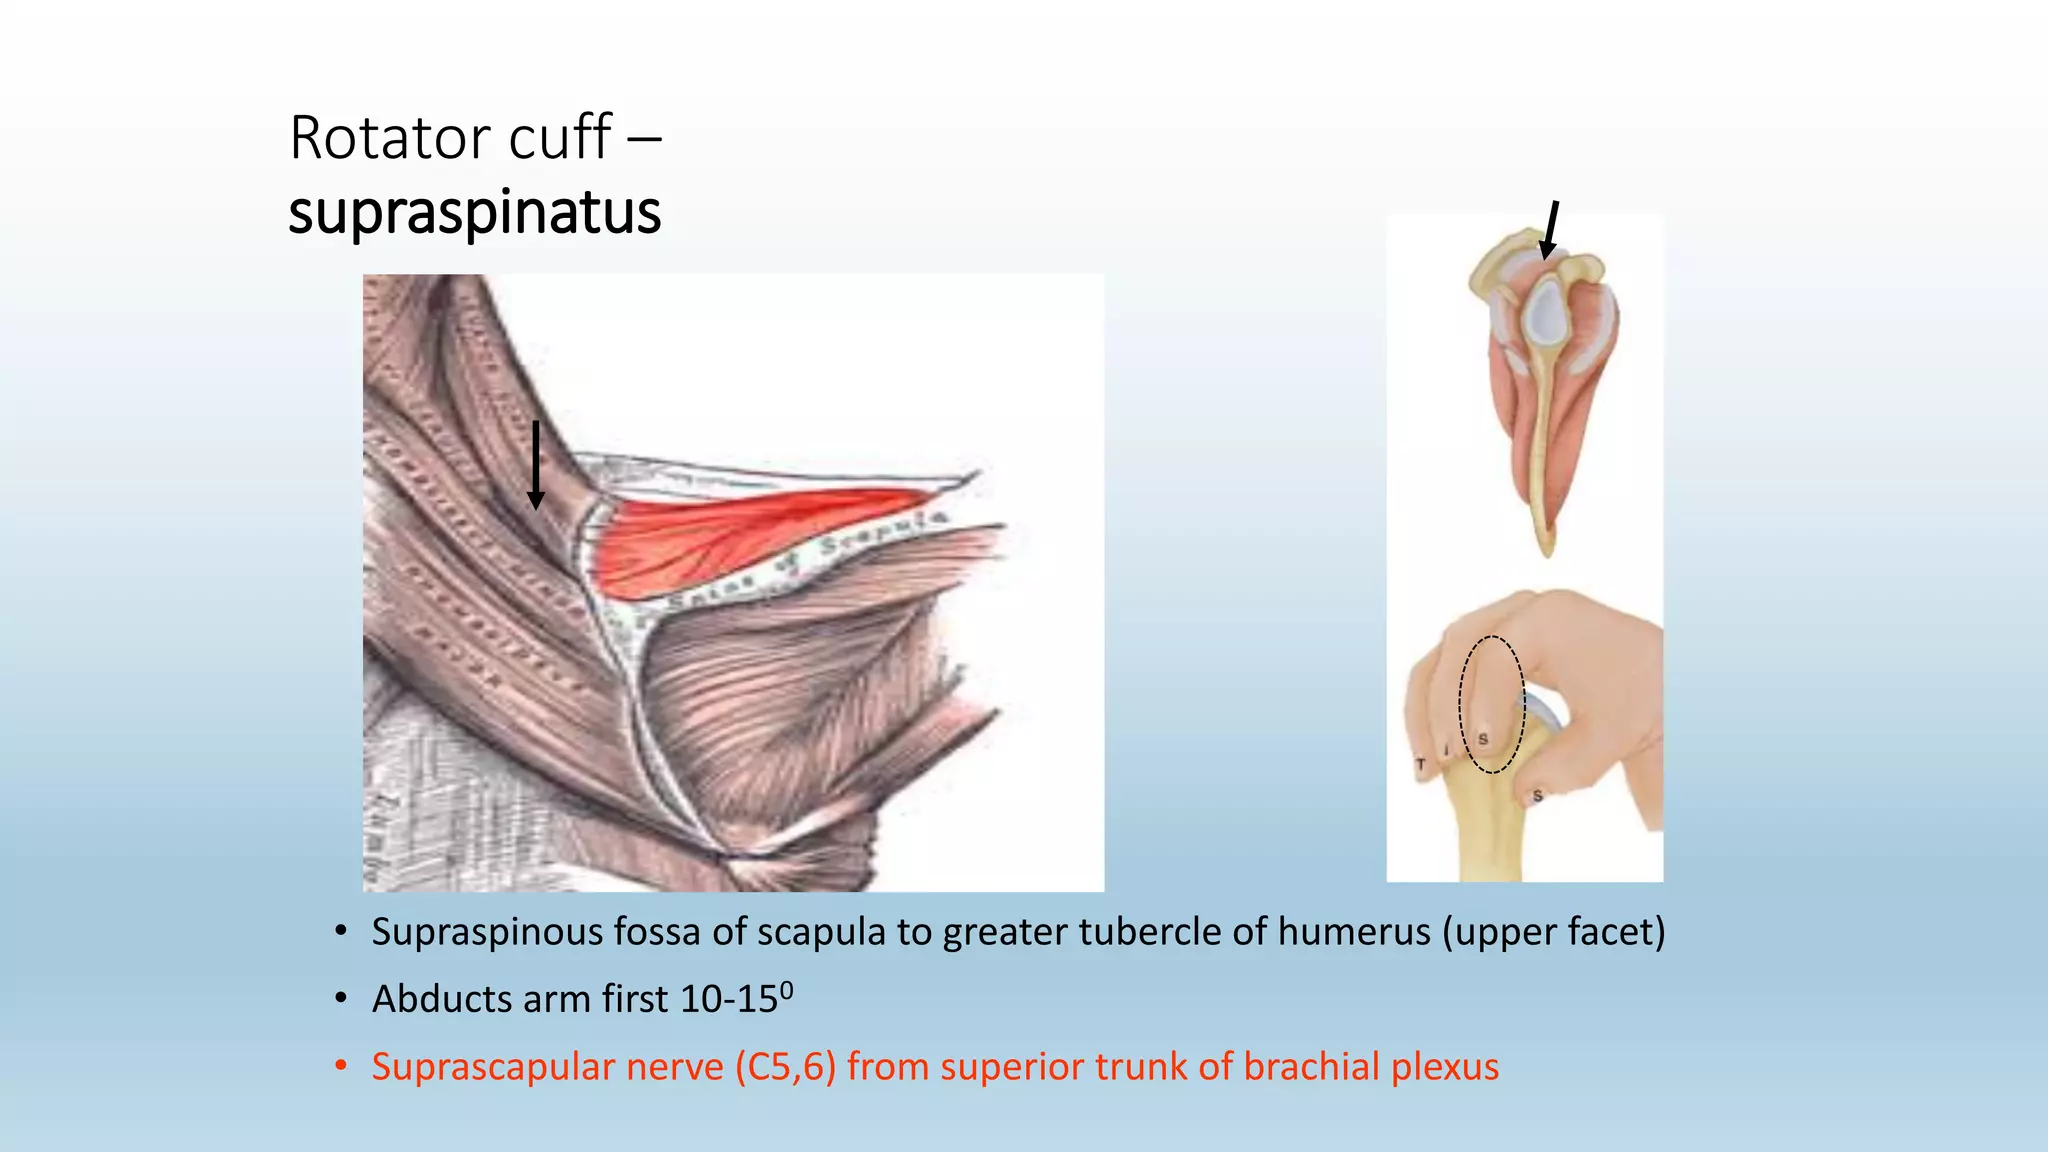

The document summarizes an anatomy revision session on the upper limb. It discusses various muscles of the upper limb including their origins, insertions, innervations and functions. Key muscles covered include the pectoralis major and minor, serratus anterior, deltoid, biceps brachii, brachialis, coracobrachialis, and triceps. It also discusses the rotator cuff muscles and muscles of the forearm including flexor carpi ulnaris and radialis. The session aims to help students identify upper limb muscles and understand their relations to nerves.